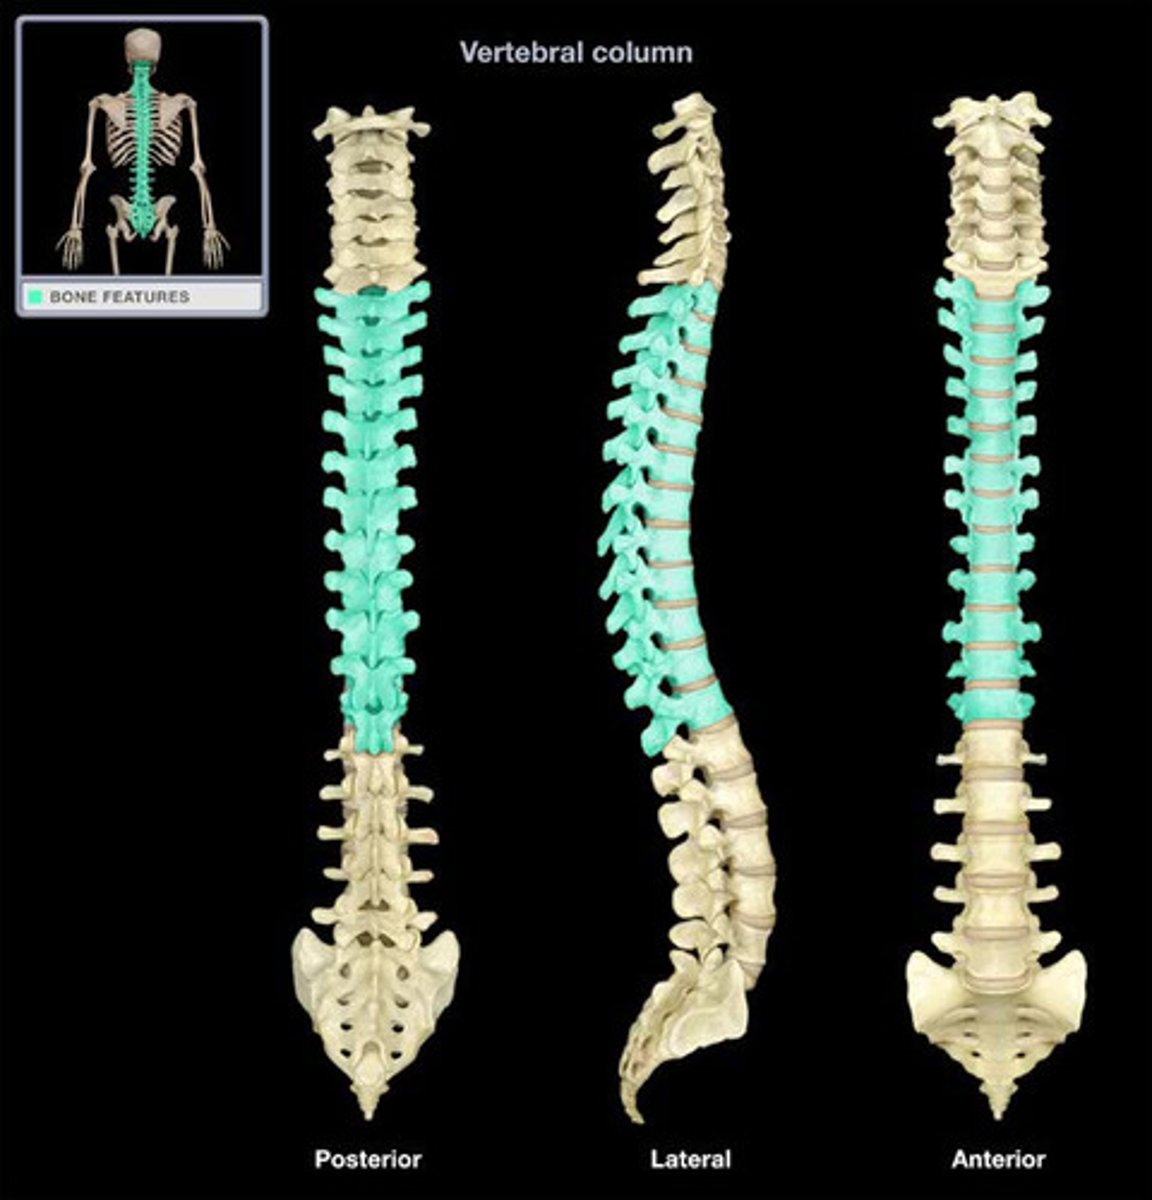

What are the sections of the vertebral column?

cervical, thoracic, lumbar, sacrum, coccyx

How many vertebrae make up the thoracic spine?

12

Which regions of the spine have CONCAVE curvatures and are described as LORDOTIC?

Which regions of the spine have CONVEX curvatures and are described as KYPHOTIC?

thoracic and sacral

increase

What is the unique characteristic of the thoracic spine?

facets for rib articulation